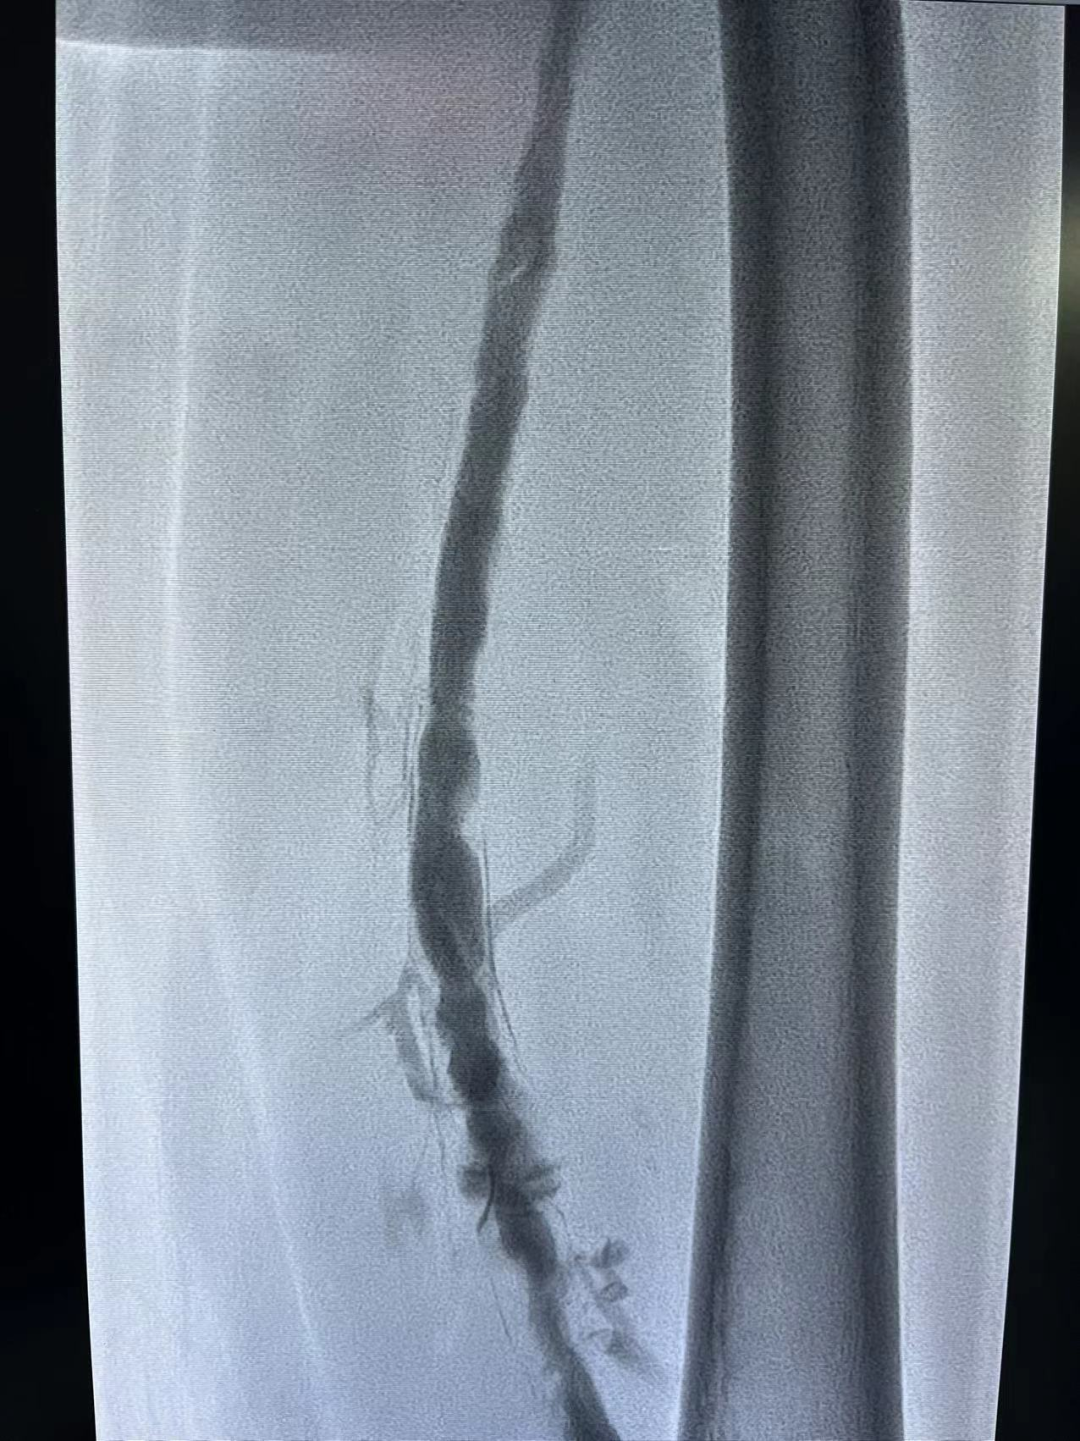

在下腔静脉滤器保护下,经腘静脉置入吸栓导管,吸出大量血栓。